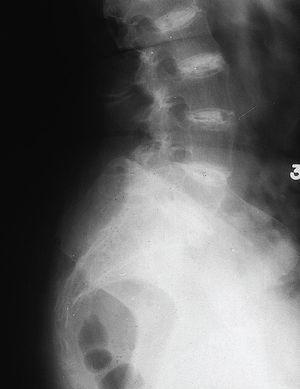

Fig. 2

En el esqueleto axial llama la atención la calcificación del disco, sobre todo a nivel dorsolumbar, pinzamiento del espacio intervertebral con colapso del disco y consiguiente fusión, y formación de cuerpos intervertebrales marginales.